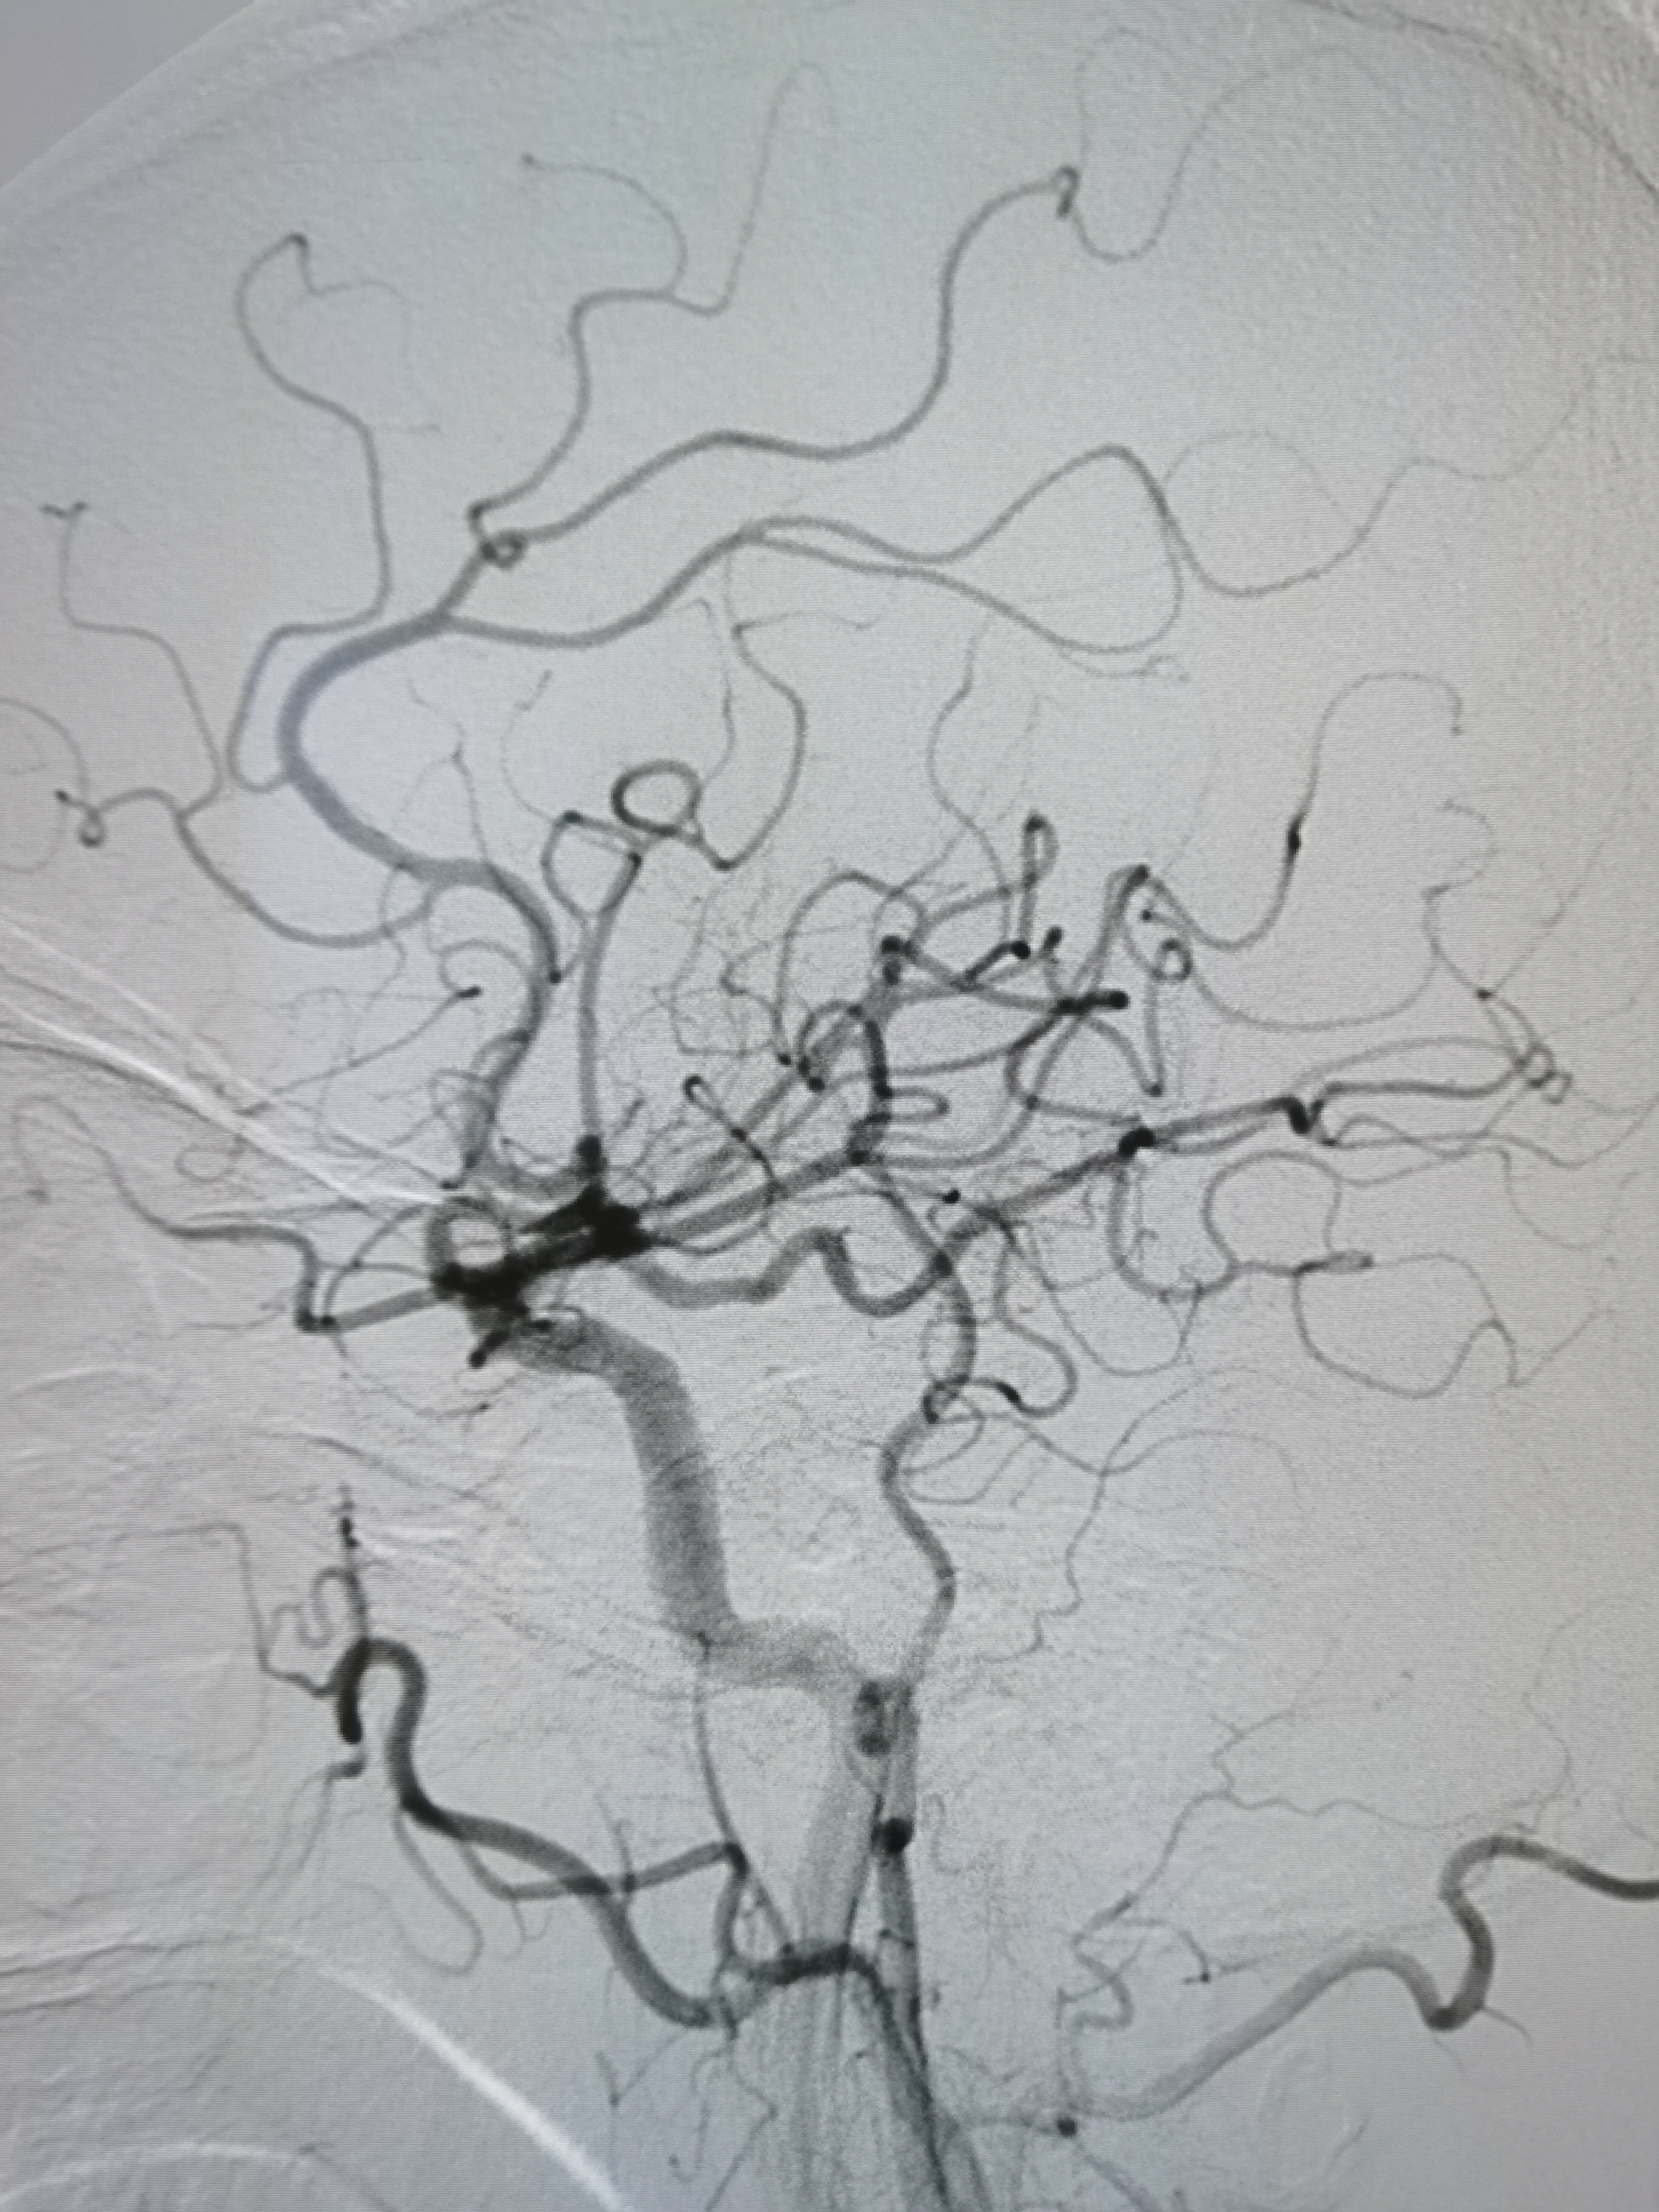

左侧胚胎型大脑后动脉,颅内血流明显改善。

支架位置形态满意,撤出保护伞,结束手术。